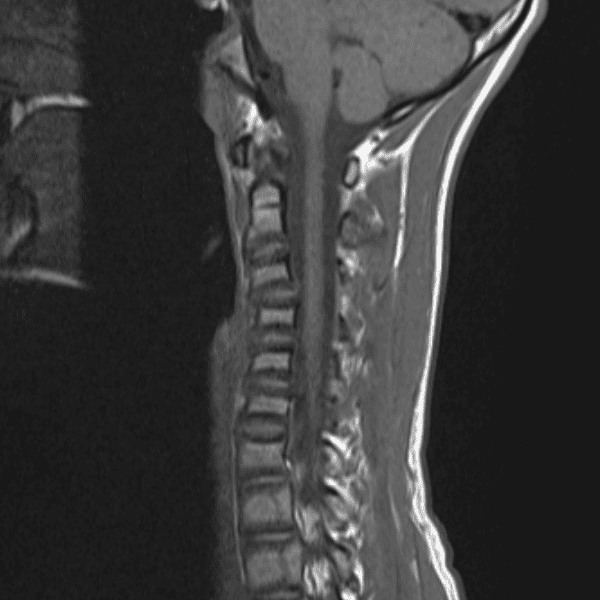

Simulates call by including subtle or difficult cases and some normals.

35 cases